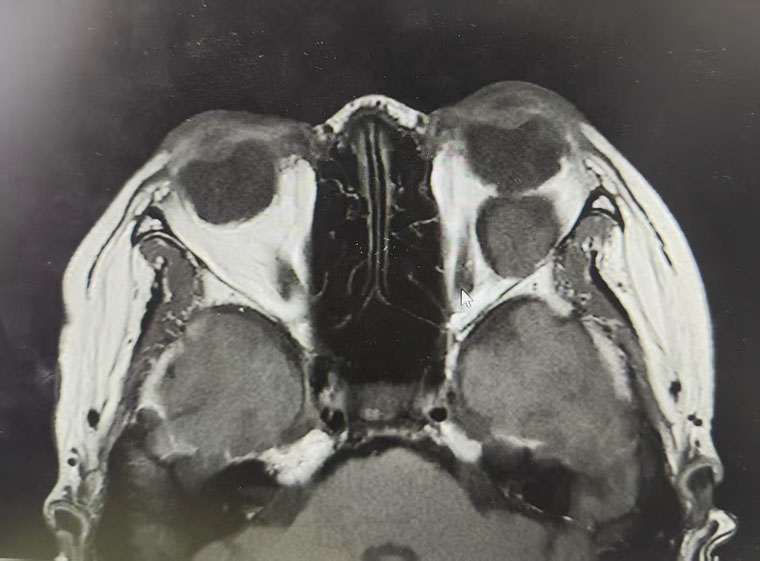

該患者因“發現右眼眼球逐漸突出2年”就診于我院,眼眶CT檢查顯示,眼球正后方隱藏著一個與眼球等大的腫物,占位效應明顯。眼球后方空間狹小、結構精密,如何在這一關鍵區域將體積較大的腫瘤完整剝離,同時保護視神經、眼外肌等重要解剖結構不受損傷,加之患者明確要求面部不能留下疤痕,這些因素均對手術精準度與微創性提出了極致挑戰。

術前

術后